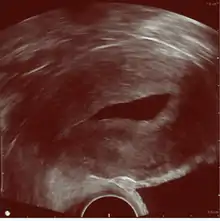

Gynecologic ultrasonography

Left hydrosalpinx on gynecologic ultrasonography